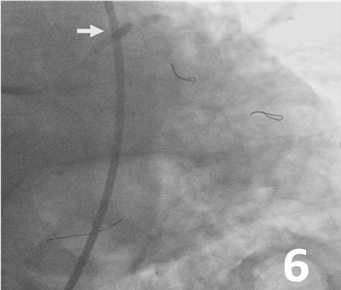

Predilatation was made from the LAD, ramus, and LCx to the left main artery with 3 Ryurei balloons (Terumo) at 8 atm (3.5 x 20 mm, 2.5 x 20 mm, and 2.5 x 15 mm, respectively) (Figure 5). A 3.0 x 32-mm synergy stent was deployed from the middle to the proximal segment of the LAD (Figure 6). Then, 3 stents were advanced and deployed simultaneously from the LAD, ramus, and LCx (Synergy 5.0 x 24 mm [Boston Scientific], Xience Sierra 3.0 x 33 mm [Abbott], and Synergy 3.5 x 16 mm, respectively) (Figure 7). Simultaneous triple-balloon (kissing) inflation at 12 atm was performed with three 2.0 x 15-mm Ryurei balloons (Figure 8); the 3 balloons were simultaneously inflated 3 times.